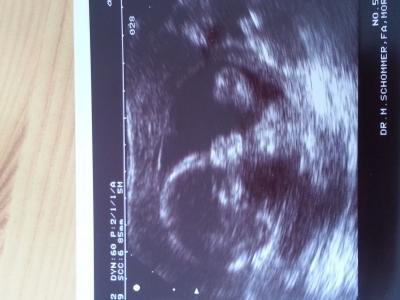

Huhu ihr lieben Baby geht es gut. Entwickelt sich super. Alle organe intakt. Herz ist bis jetzt auch in Ordnung. Und es wird ein Mädchen

Bild zu Frauenarztbericht - Forum für Oktober - Mamis